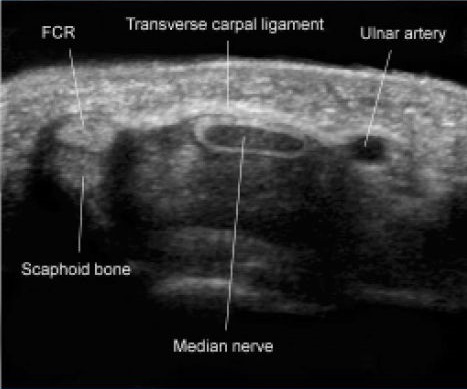

USG kanału nadgarstka – badanie popularne po publikacji wyników badań Buchbergera i wsp. ( 1991) wykazujących korelację pomiędzy funkcją a średnicą nerwu pośrodkowego. Badanie to dostarcza również informacji o architekturze i korelacjach w operowanym polu anatomicznym.

Badanie usg kanału nadgarstka